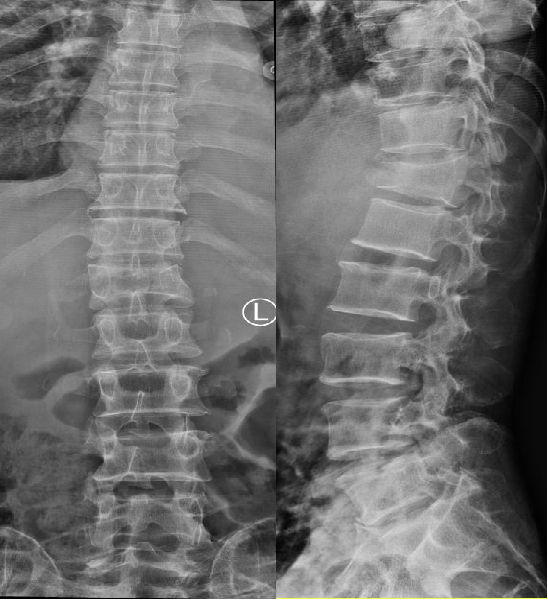

一、X 线:骨折筛查的 “侦察兵”

第一眼侦察:快速发现椎体形态改变,如椎体高度丢失、楔形变或后凸畸形。

初步定位:确定骨折椎体的位置,排除脊柱肿瘤等其他病变。

72 岁的王某腰背痛 3 天,X 线显示L1椎体 “楔形变”,高度丢失约 30%,初步诊断为 OVCF。但 X 线无法判断骨折是否新鲜,也看不清椎体后壁是否破裂,这时就需要 CT 和 MRI 出场了。

无法区分新鲜骨折与陈旧性骨折(椎体可能因多次骨折呈现“叠罗汉” 样改变)。 -

对细微骨折(如椎弓根骨折)或椎管内情况显示不清。